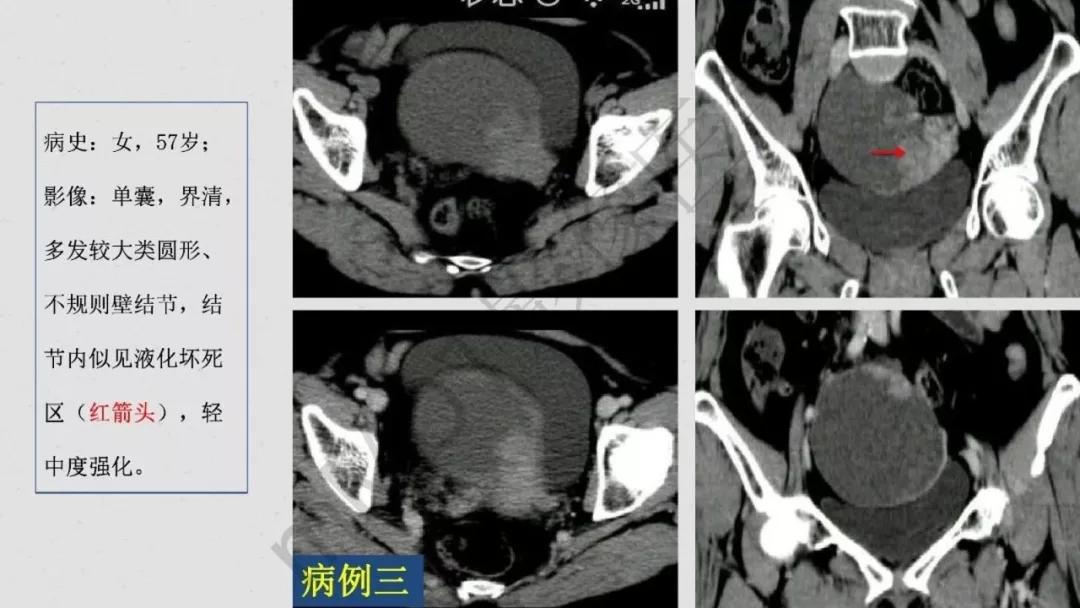

上皮性肿瘤:最常见,恶性多(卵巢癌),良性少。好发于50Y以上,发现时多为中晚期。多呈囊性或以囊性为主的囊实性肿块,完全实性者少见。形态多数不规则,边界模糊,囊壁及房间隔常不规则增厚,菜花样肿物或壁结节,囊实性区域分界不清,实性肿瘤常有不规则低密度或坏死区,可有边界模糊沙粒状或块状钙化,中-高度强化。良性者边界清晰,囊壁薄光整,无壁结节,实性部分呈无或轻度强化。

病理:浆液性囊腺癌

病理:颗粒细胞瘤